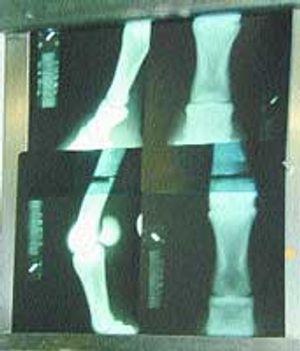

A look at the pros and cons of standing vs. recumbent magnetic resonance imaging systems.